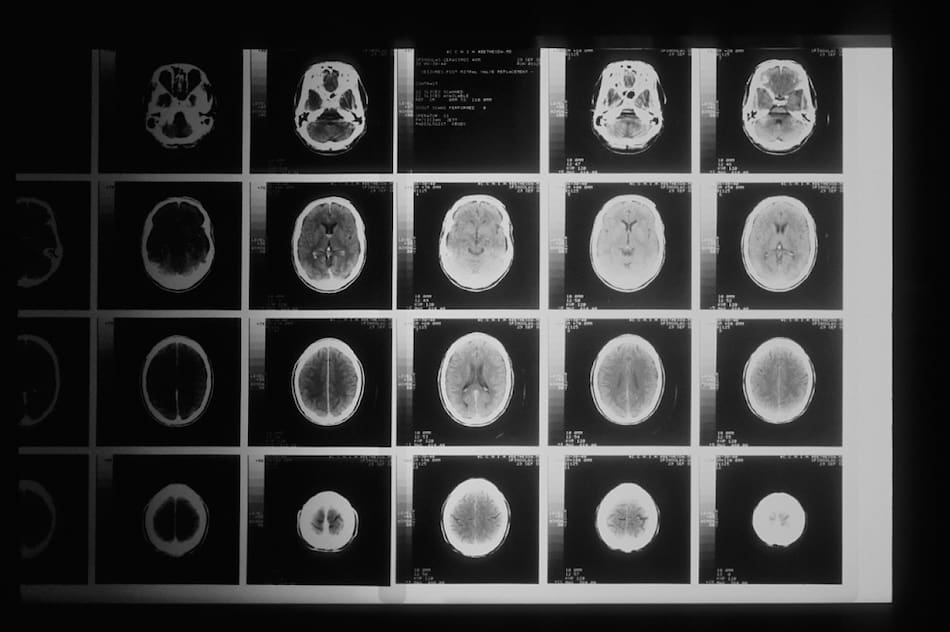

El glioblastoma es un agresivo tipo de cáncer cerebral difícil de tratar debido a su naturaleza agresiva y capacidad para crecer y diseminarse rápidamente.

Se trata del glioblastoma, un tipo de cáncer en el cerebro altamente agresivo cuyo pronóstico es generalmente desalentador.

Tumor cerebral. Foto: Unsplash.